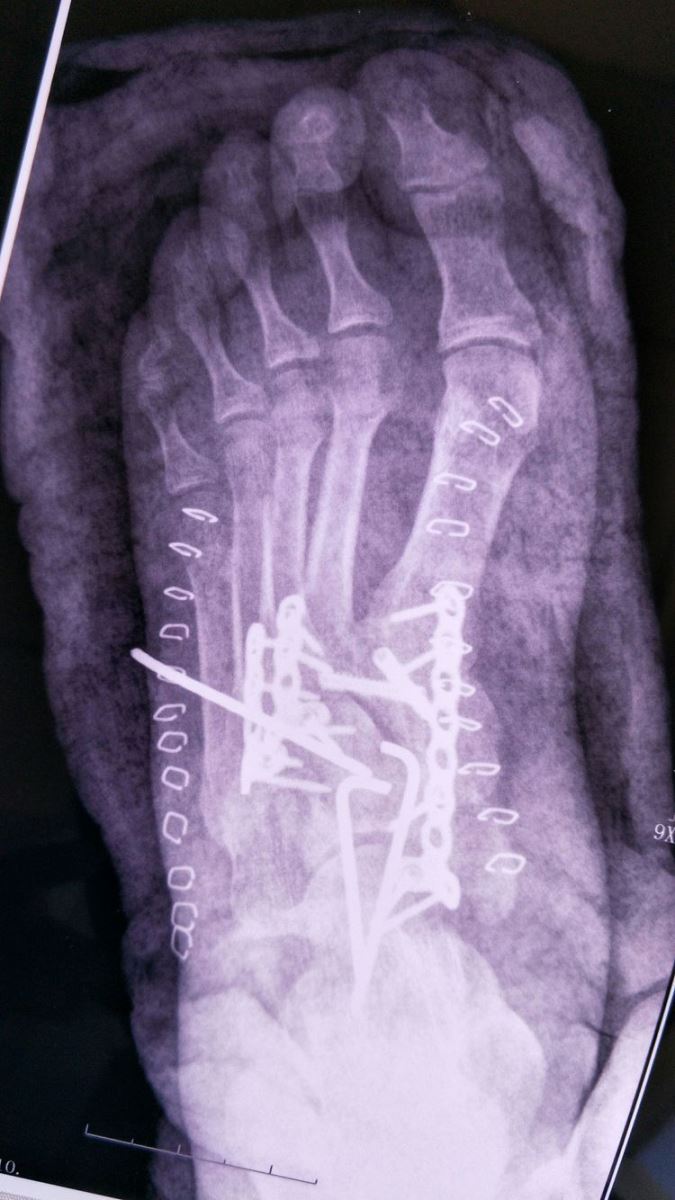

术后X光:Chaopart关节脱位纠正,固定良好,跖跗关节脱位纠正,固定良好。